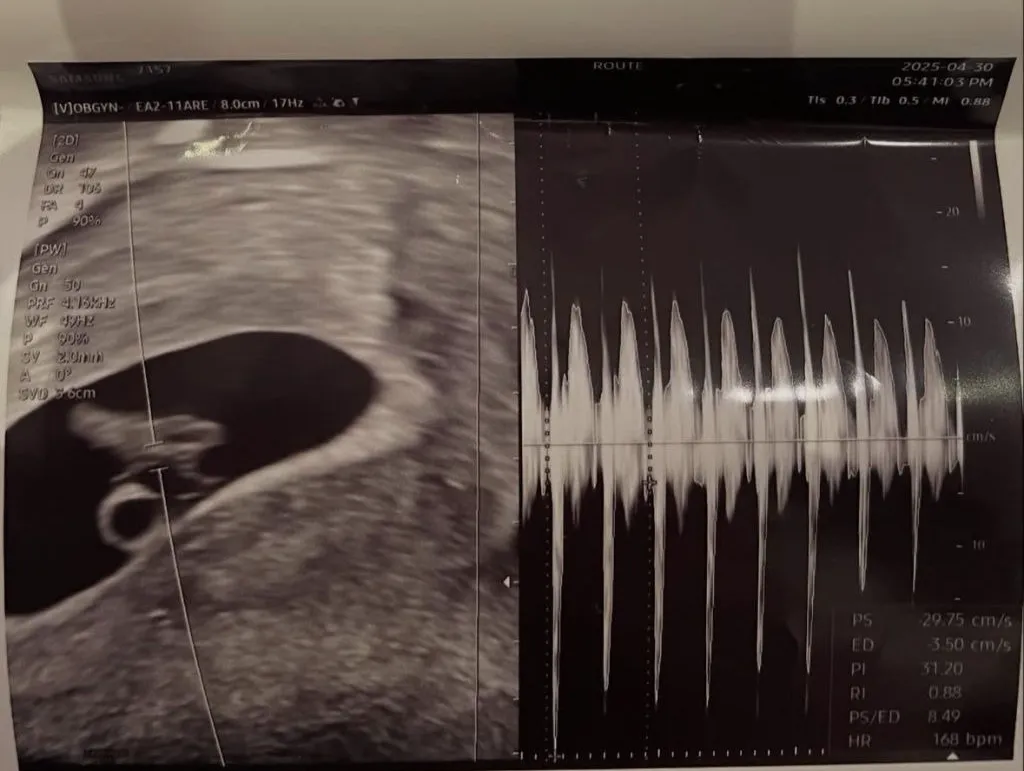

서은우는 “축하해주셔서 감사합니다”라며 초음파 사진, 그리고 남자친구와 찍은 사진을 올렸다.